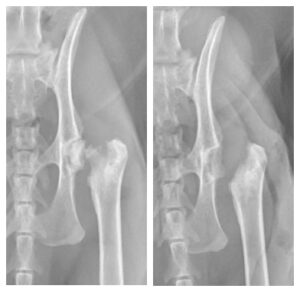

Femoral Head and Neck Ostectomy (FHO):

An FHO procedure involves surgical excision of the femoral head and neck (the top portion of the thigh bone that connects it to the hip joint) (Figure 3). This removes the site of the fracture and prevents bone-on-bone contact from the remaining cut surface of the thigh bone against the pelvis. As a portion of the hip joint is no longer present, this creates a false joint where surrounding muscles and other soft tissues hold the site together and allow movement. Because this is no longer a true joint however, it will not have a normal range of motion compared to an unaffected hip and the operated limb will be shorter than the limb on the other side. Physical rehabilitation with a veterinary specialist is recommended after an FHO procedure to retain the greatest range of motion possible post-operatively.